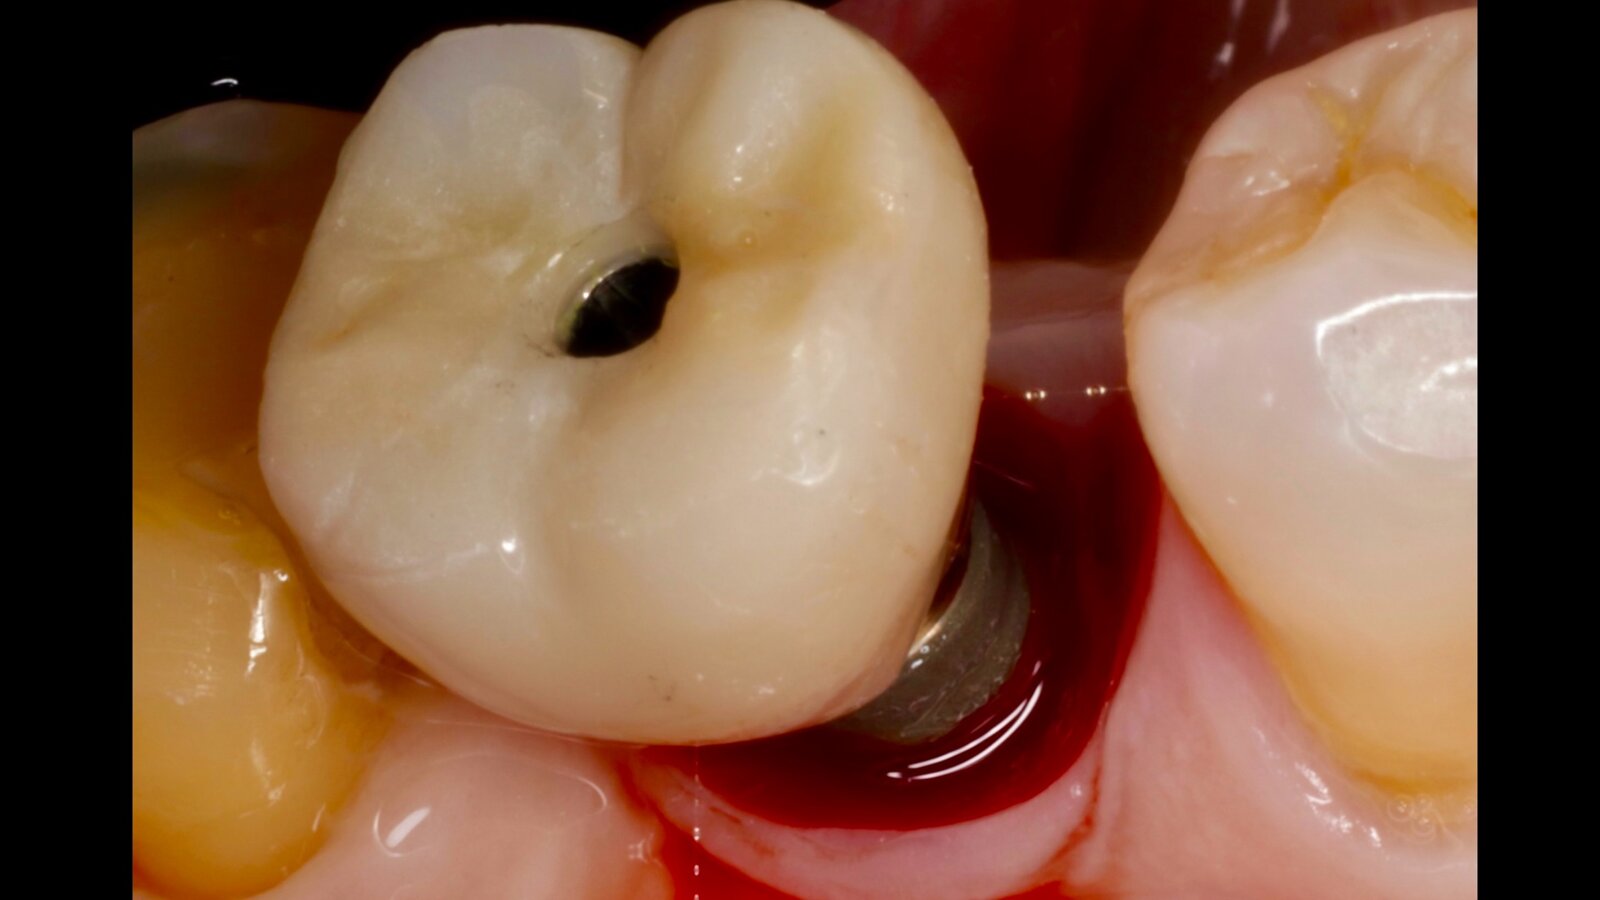

Figura 1. Evidencia clínica de periimplantitis en un paciente con diabetes mellitus tipo 1. Imágenes: Iván Herrera

La periimplantitis es una enfermedad inflamatoria crónica que afecta los tejidos blandos y duros que rodean los implantes dentales osteointegrados. A pesar de los elevados índices de supervivencia reportados para los implantes dentales, la creciente prevalencia de las enfermedades periimplantarias ha generado una preocupación sustancial en la práctica clínica que se refleja en la literatura científica contemporánea. La evidencia actual respalda un modelo etiopatogénico multifactorial en el que la interacción entre el biofilm bacteriano, los factores locales asociados al diseño protésico y las condiciones sistémicas del paciente determinan la progresión de la enfermedad periimplantaria (Figura 1).